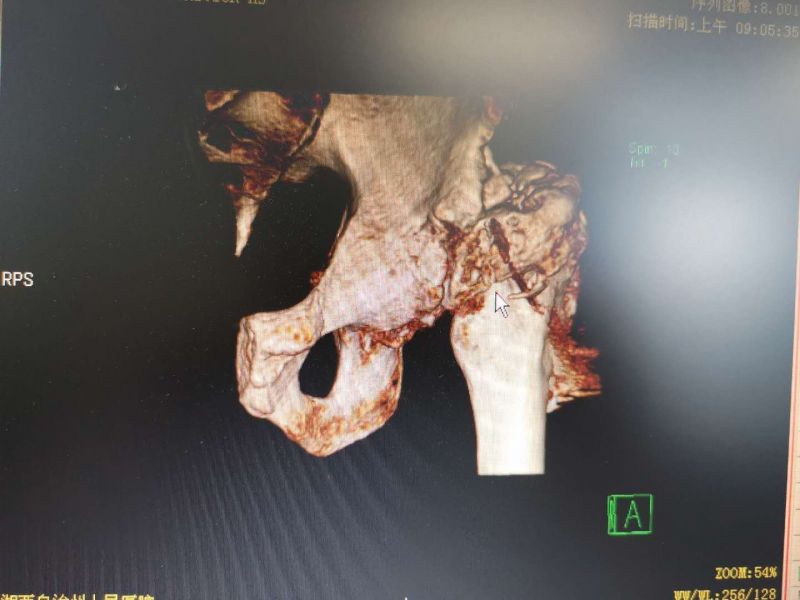

患者慕名找到湘西州人民医院骨一科主任赵峻主任医师,希望通过赵峻主任医师的治疗,能够自由行走,不再受疼痛的困扰。赵峻主任医师带领其团队,对患者进行仔细的体格检查,并仔细阅读了患者的相关影像学资料,发现患者左髋关节活动度已完全尚失,左下肢明显外旋畸形,且左下肢较对侧短了近6cm。经赵峻主任医师及其团队讨论后,制定详细的手术方案。完善术前检查后,于4月19日在麻醉科及手术室共同协助下行左侧人工髋关节置换术,虽然术前已经对术中可能出现的困难进行了充分的准备,但手术的复杂程度远远超过预期。面对术中各种挑战,赵峻主任带领其团队,沉着应对,最终历时4个小时,顺利完成手术。术后行X线片检查提示患者左下肢长度较前明显恢复,且在骨一科全体医护人员的精心指导下积极行功能锻炼,患者左侧髋关节活动度明显改善。最终患者健康出院。

患者术前CT 患者术前CT